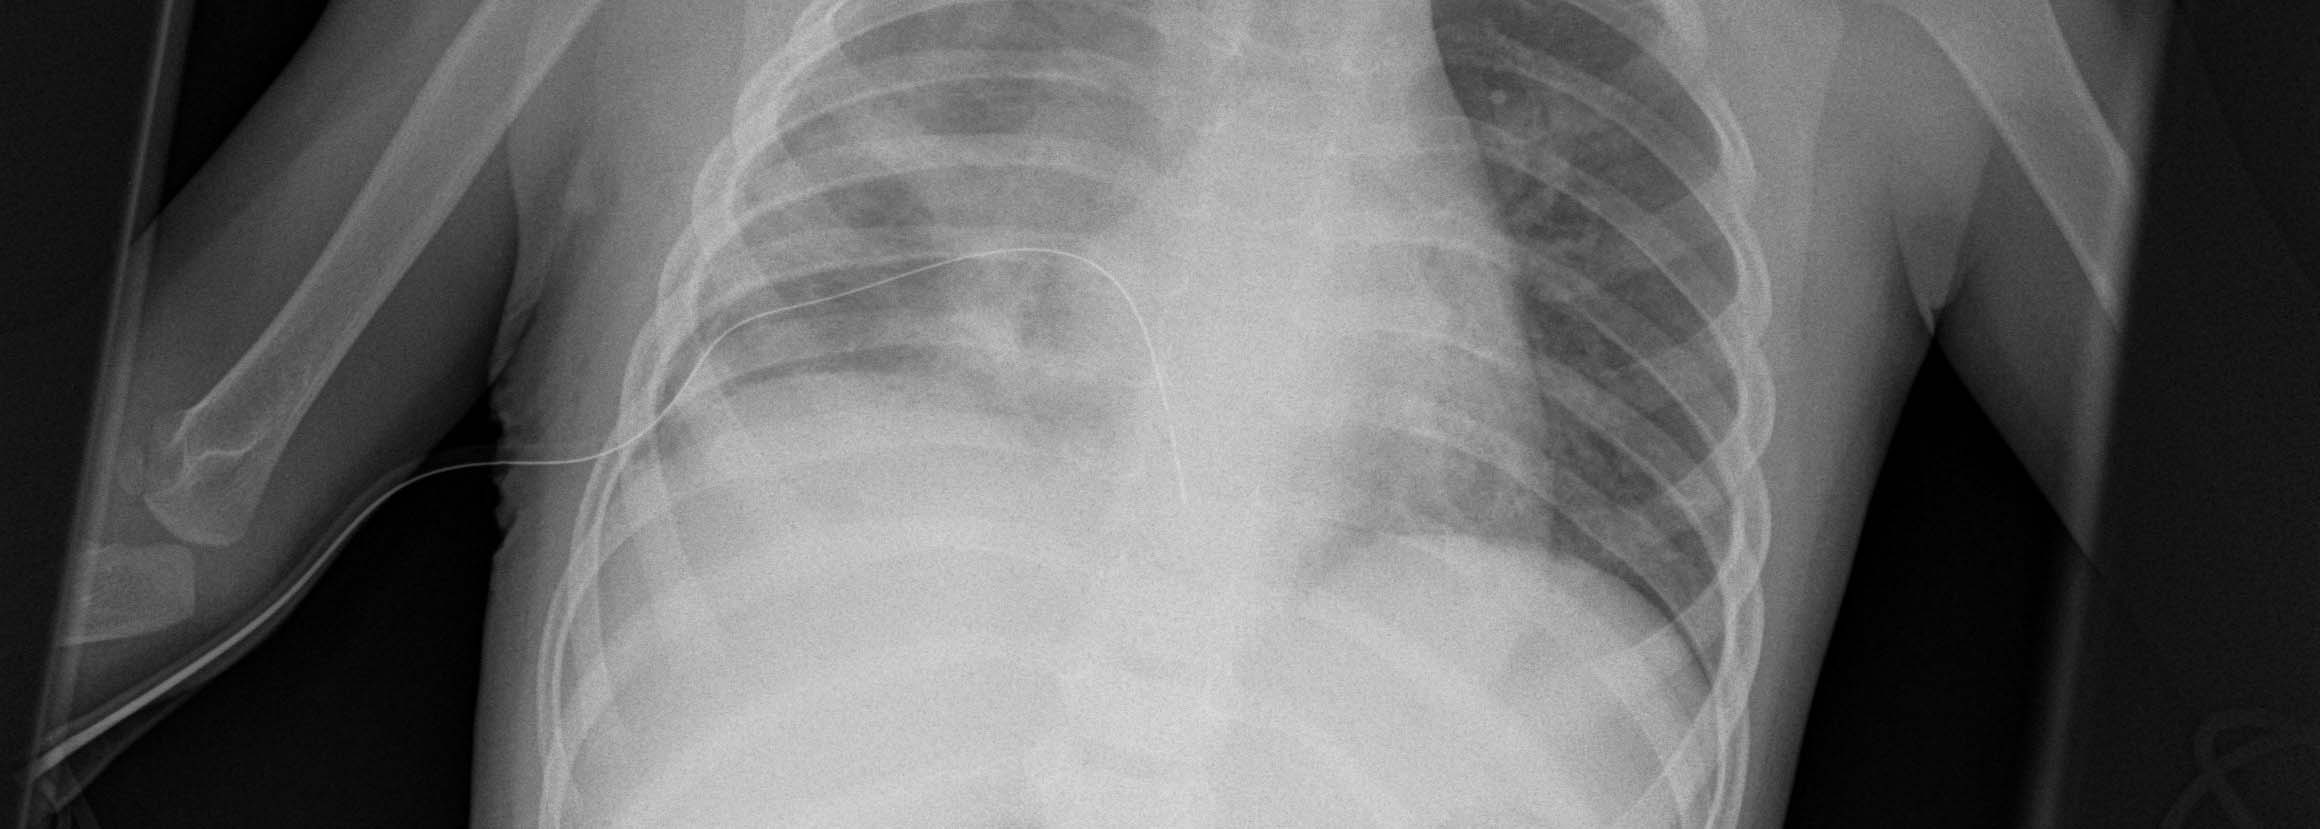

Thoracic Surgery in Children

Together with the specialists in pediatric surgery and the pediatric clinic, we attend to children with thoracic diseases and perform thoracic surgery when appropriate after thorough examination and analysis of the disease. All thoracic surgical procedures including minimally invasive keyhole surgery are used here. Our little patients benefit from the vast experience of many specialists from a wide variety of medical disciplines who specialize in the treatment of children.